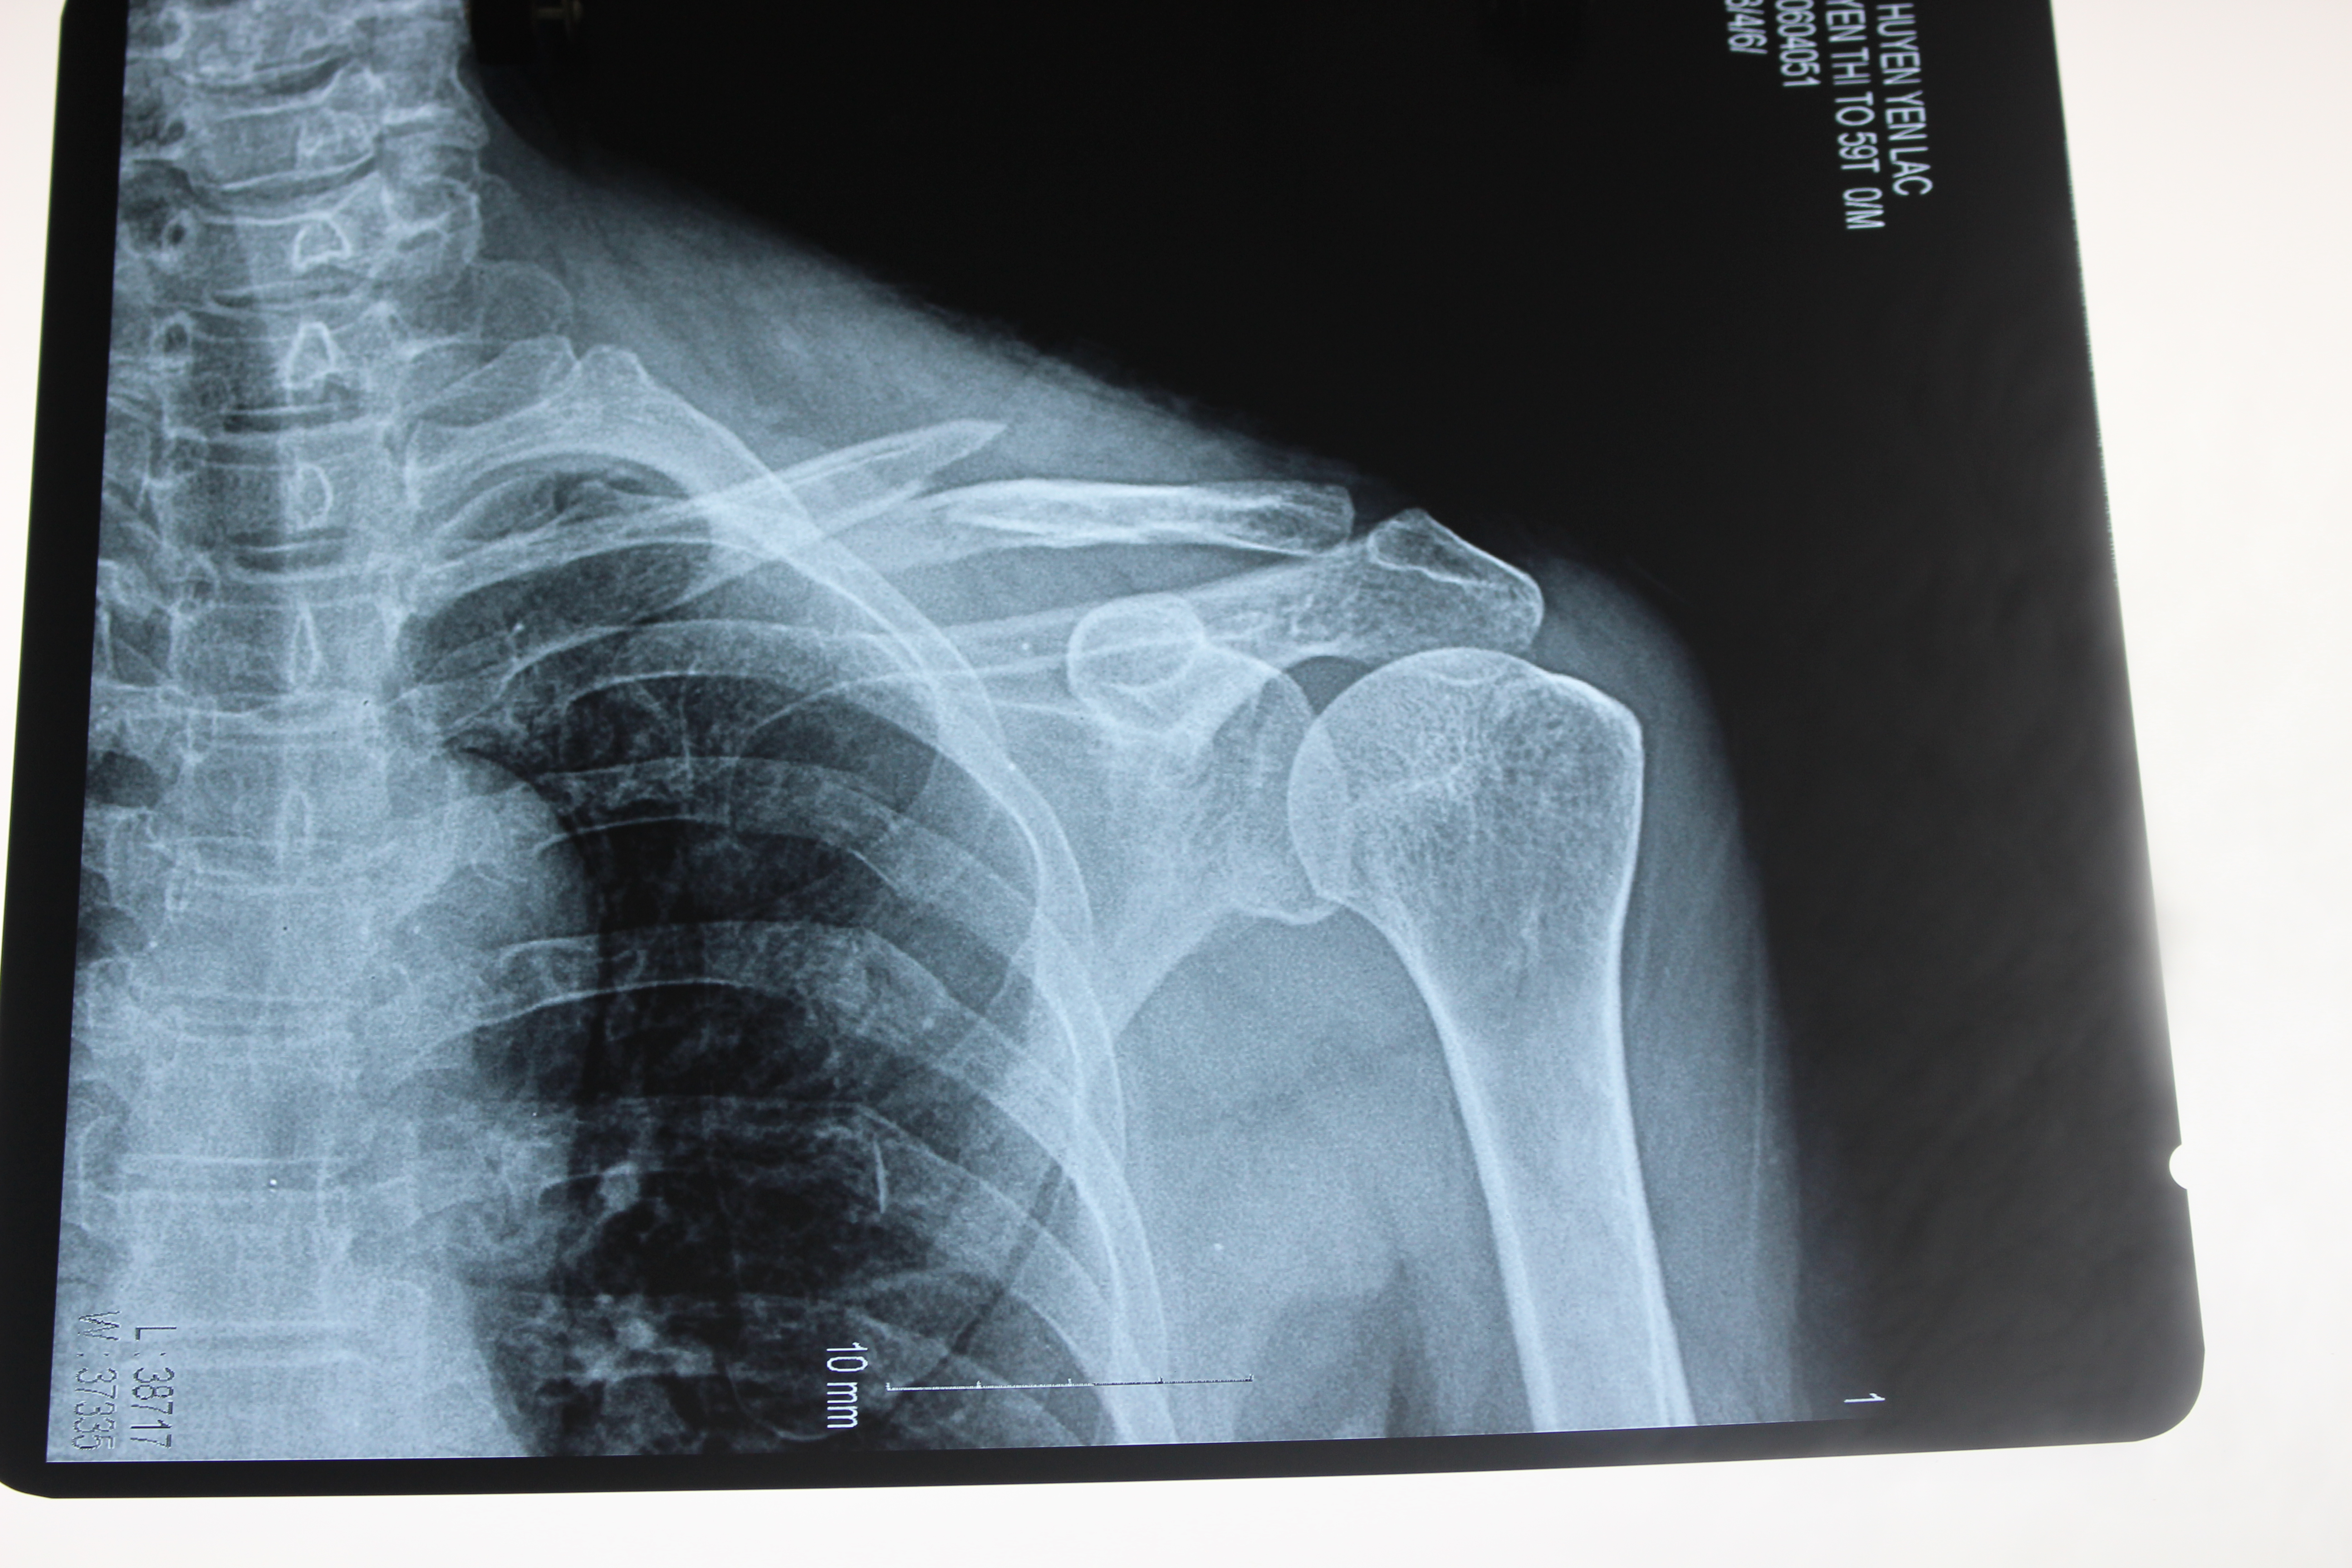

Chiều ngày 5 tháng 6 năm 2016. Tại khoa ngoại tổng hợp gây mê hồi sức- Trung tâm y tế huyện Yên Lạc. Bác sỹ CKI Nguyễn Hoàng Phương cùng ê kíp đã tiến hành phẫu thuật kết hợp xương đòn trái cho bệnh nhân nữ 59 tuổi – Thôn Nho Lẻ – xã Tam Hồng – Huyện Yên Lạc – tỉnh Vĩnh Phúc. Bệnh nhân vào viện với lý do đau vai trái, hạn chế vận động, sau một tai nạn giao thông, kèm theo tiền sử tăng huyết áp đã điều trị nhiều năm. Qua thăm khám và kết quả chụp Xquang cho thấy hình ảnh gẫy 1/3 giữa xương đòn trái. Sau khi tư vấn kỹ cho bệnh nhân và gia đình, bệnh nhân đã được các bác sỹ tiến hành phẫu thuật kết hợp xương đòn trái, sau phẫu thuật bệnh nhân ổn định, đỡ đau nhiều, sức khỏe tiến triển tốt.

Một số hình ảnh phẫu thuật kết hợp xương đòn trái.